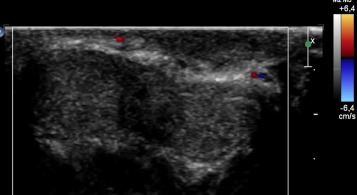

O diagnóstico da TVDSP está alicerçado na história clínica e exame físico. O eco‐Doppler é útil, principalmente nos casos em que o diagnóstico não é por si só evidente, na medida em que pode revelar uma veia não compressível ou ausência de fluxo no interior da mesma (Figura 1  and Figura 2 ). A trombose pode ocorrer na proximidade do sulco coronal, ao nível da base peniana ou pode estar presente ao longo de todo o pénis11 . Na nossa opinião e de acordo com outras publicações, outro tipo de provas complementares mais agressivas, como biopsia da zona, não são necessárias. Provas de imagiologia adicionais podem ser adequadas no caso de recorrência, ou se pretendemos descartar tumoração pélvica.

Trombose da veia superficial dorsal do pénis.

Figura 1.

Eco‐Doppler peniano transversal. Ausência de fluxo VS.

Figura 2.

Perante a suspeita de doença de Mondor peniana, solicitámos eco‐Doppler, que mostrou sinais de espessamento de paredes da veia superficial dorsal do pénis, especialmente na sua porção distal com ausência de fluxo venoso.